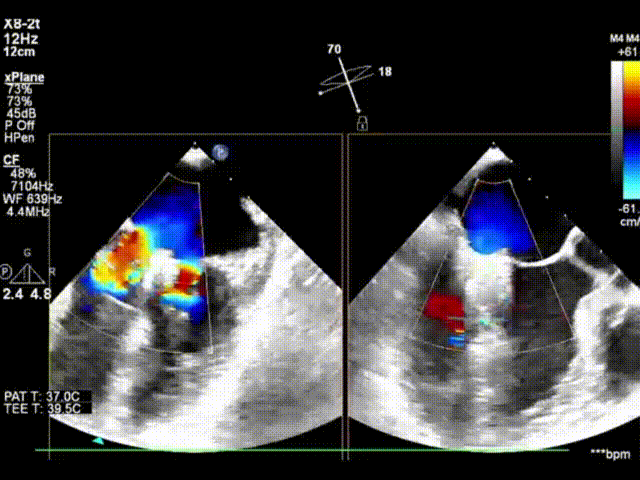

术前心超显示大量二尖瓣反流(反流宽度约1.8cm)

X-plane模式外科视角下,跨瓣器顺利跨瓣,第一个ValveClamp夹合器上下夹定位夹合

X-plane及3D模式外科视角下,跨瓣器顺利跨瓣,第二个ValveClamp夹合器上下夹定位夹合

夹合后3D左房观,反流减少至轻微,跨瓣压差PGmax:6mmHg,PGmean:2mmHg